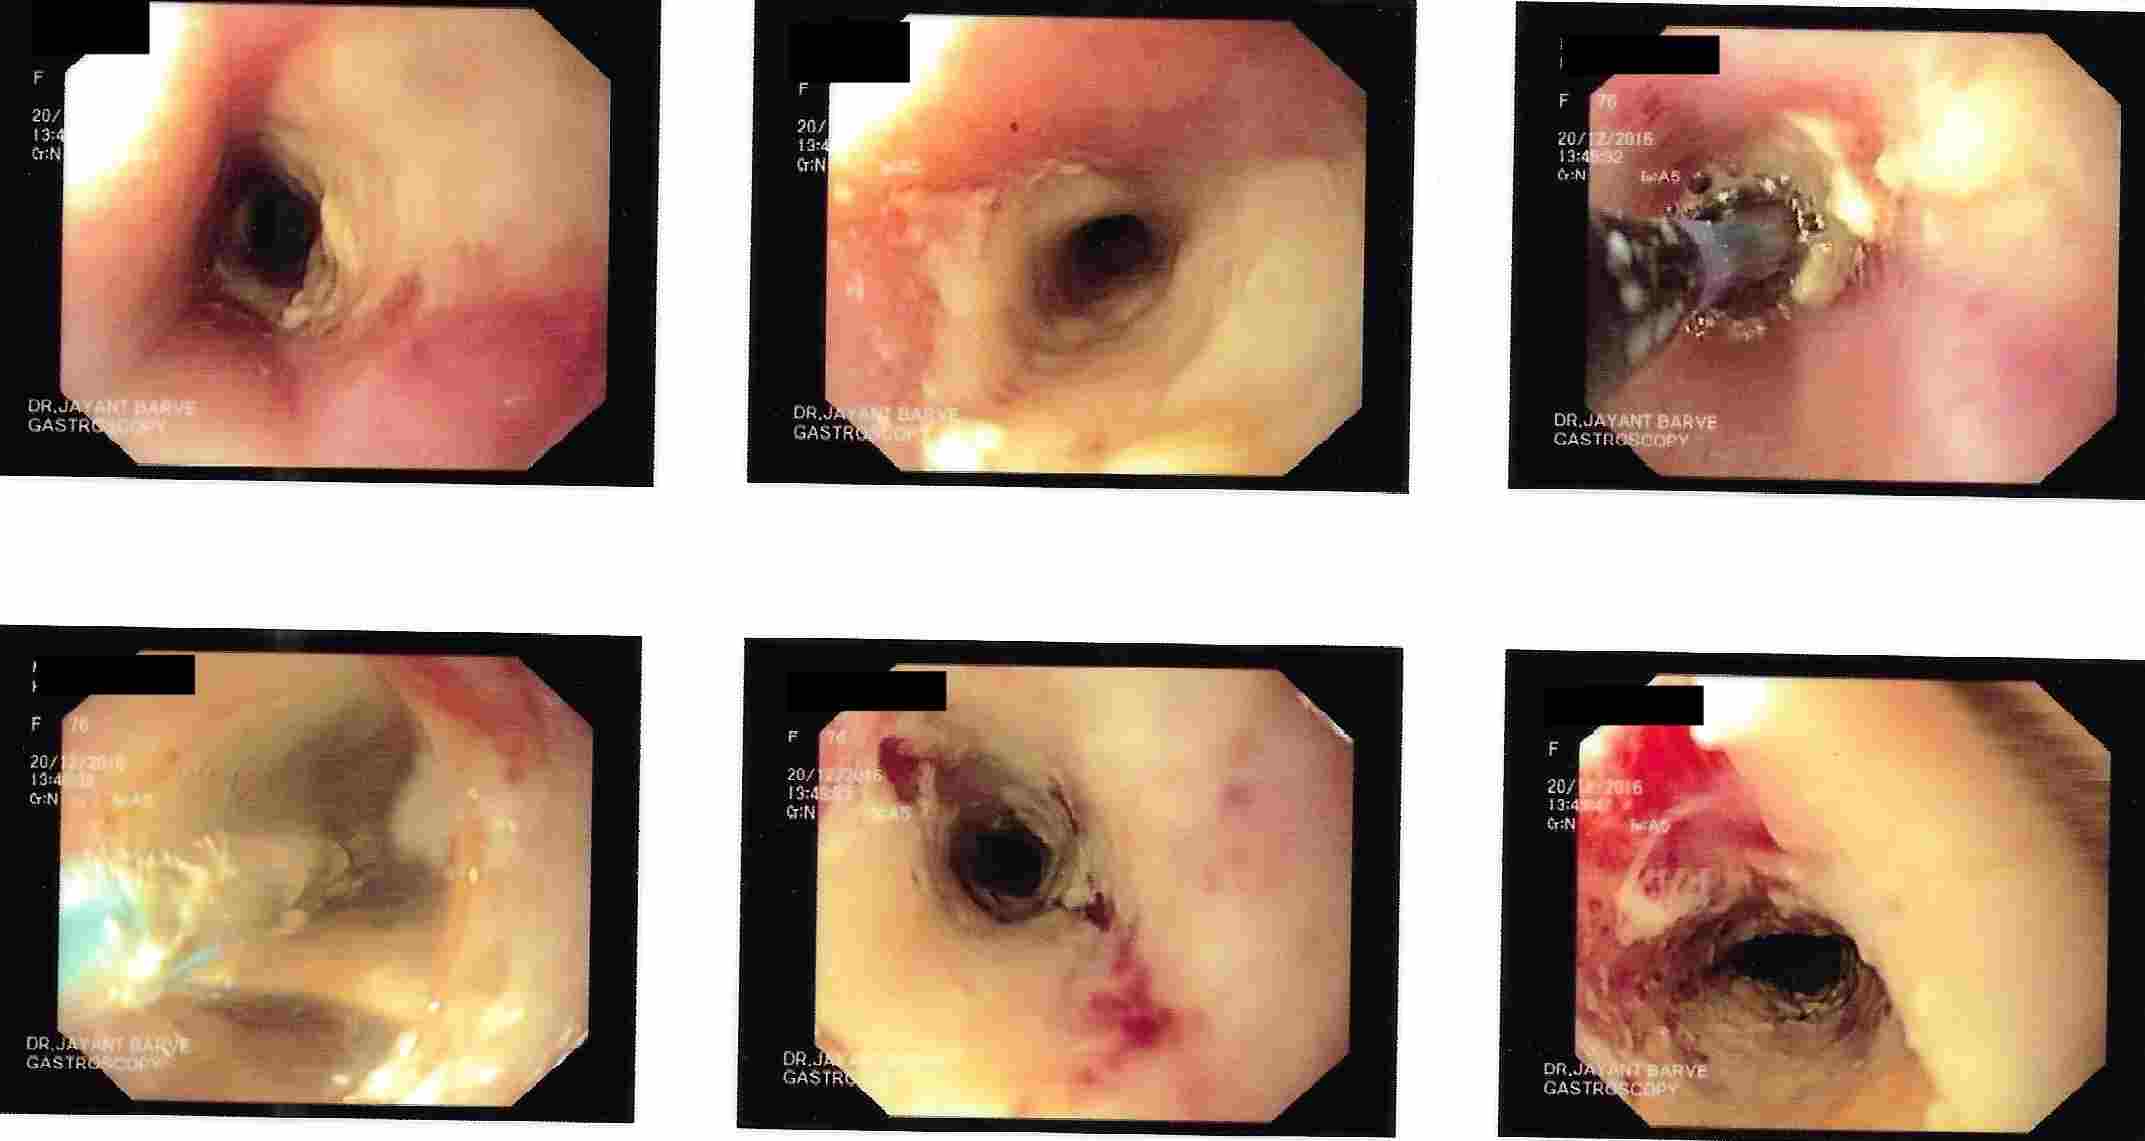

3. Difficulty in swallowing : This is considered as a serious symptom at any age group.

This can be due to severe acidic ulcerations, narrowing of the food passage due to non cancer or

cancerous lesion or pressure on the food pipe from outside.

Cancerous Lesion - Balloon Dilatation as a Palliative Treatment

Cancerous Lesion - Metal Stent as a Palliative Treatment

Cancerous Lesion - Metal Stent as a Palliative Treatment

Cancerous Lesion - Metal Stent as a Palliative Treatment